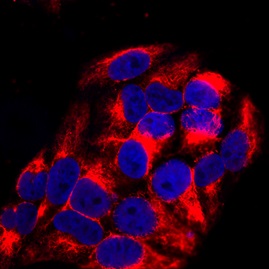

ApplicationsFlow Cytometry, Western Blot, ImmunoCytoChemistry, ImmunoHistoChemistry

- ApplicationsFlow Cytometry, Western Blot, ImmunoCytoChemistry, ImmunoHistoChemistry